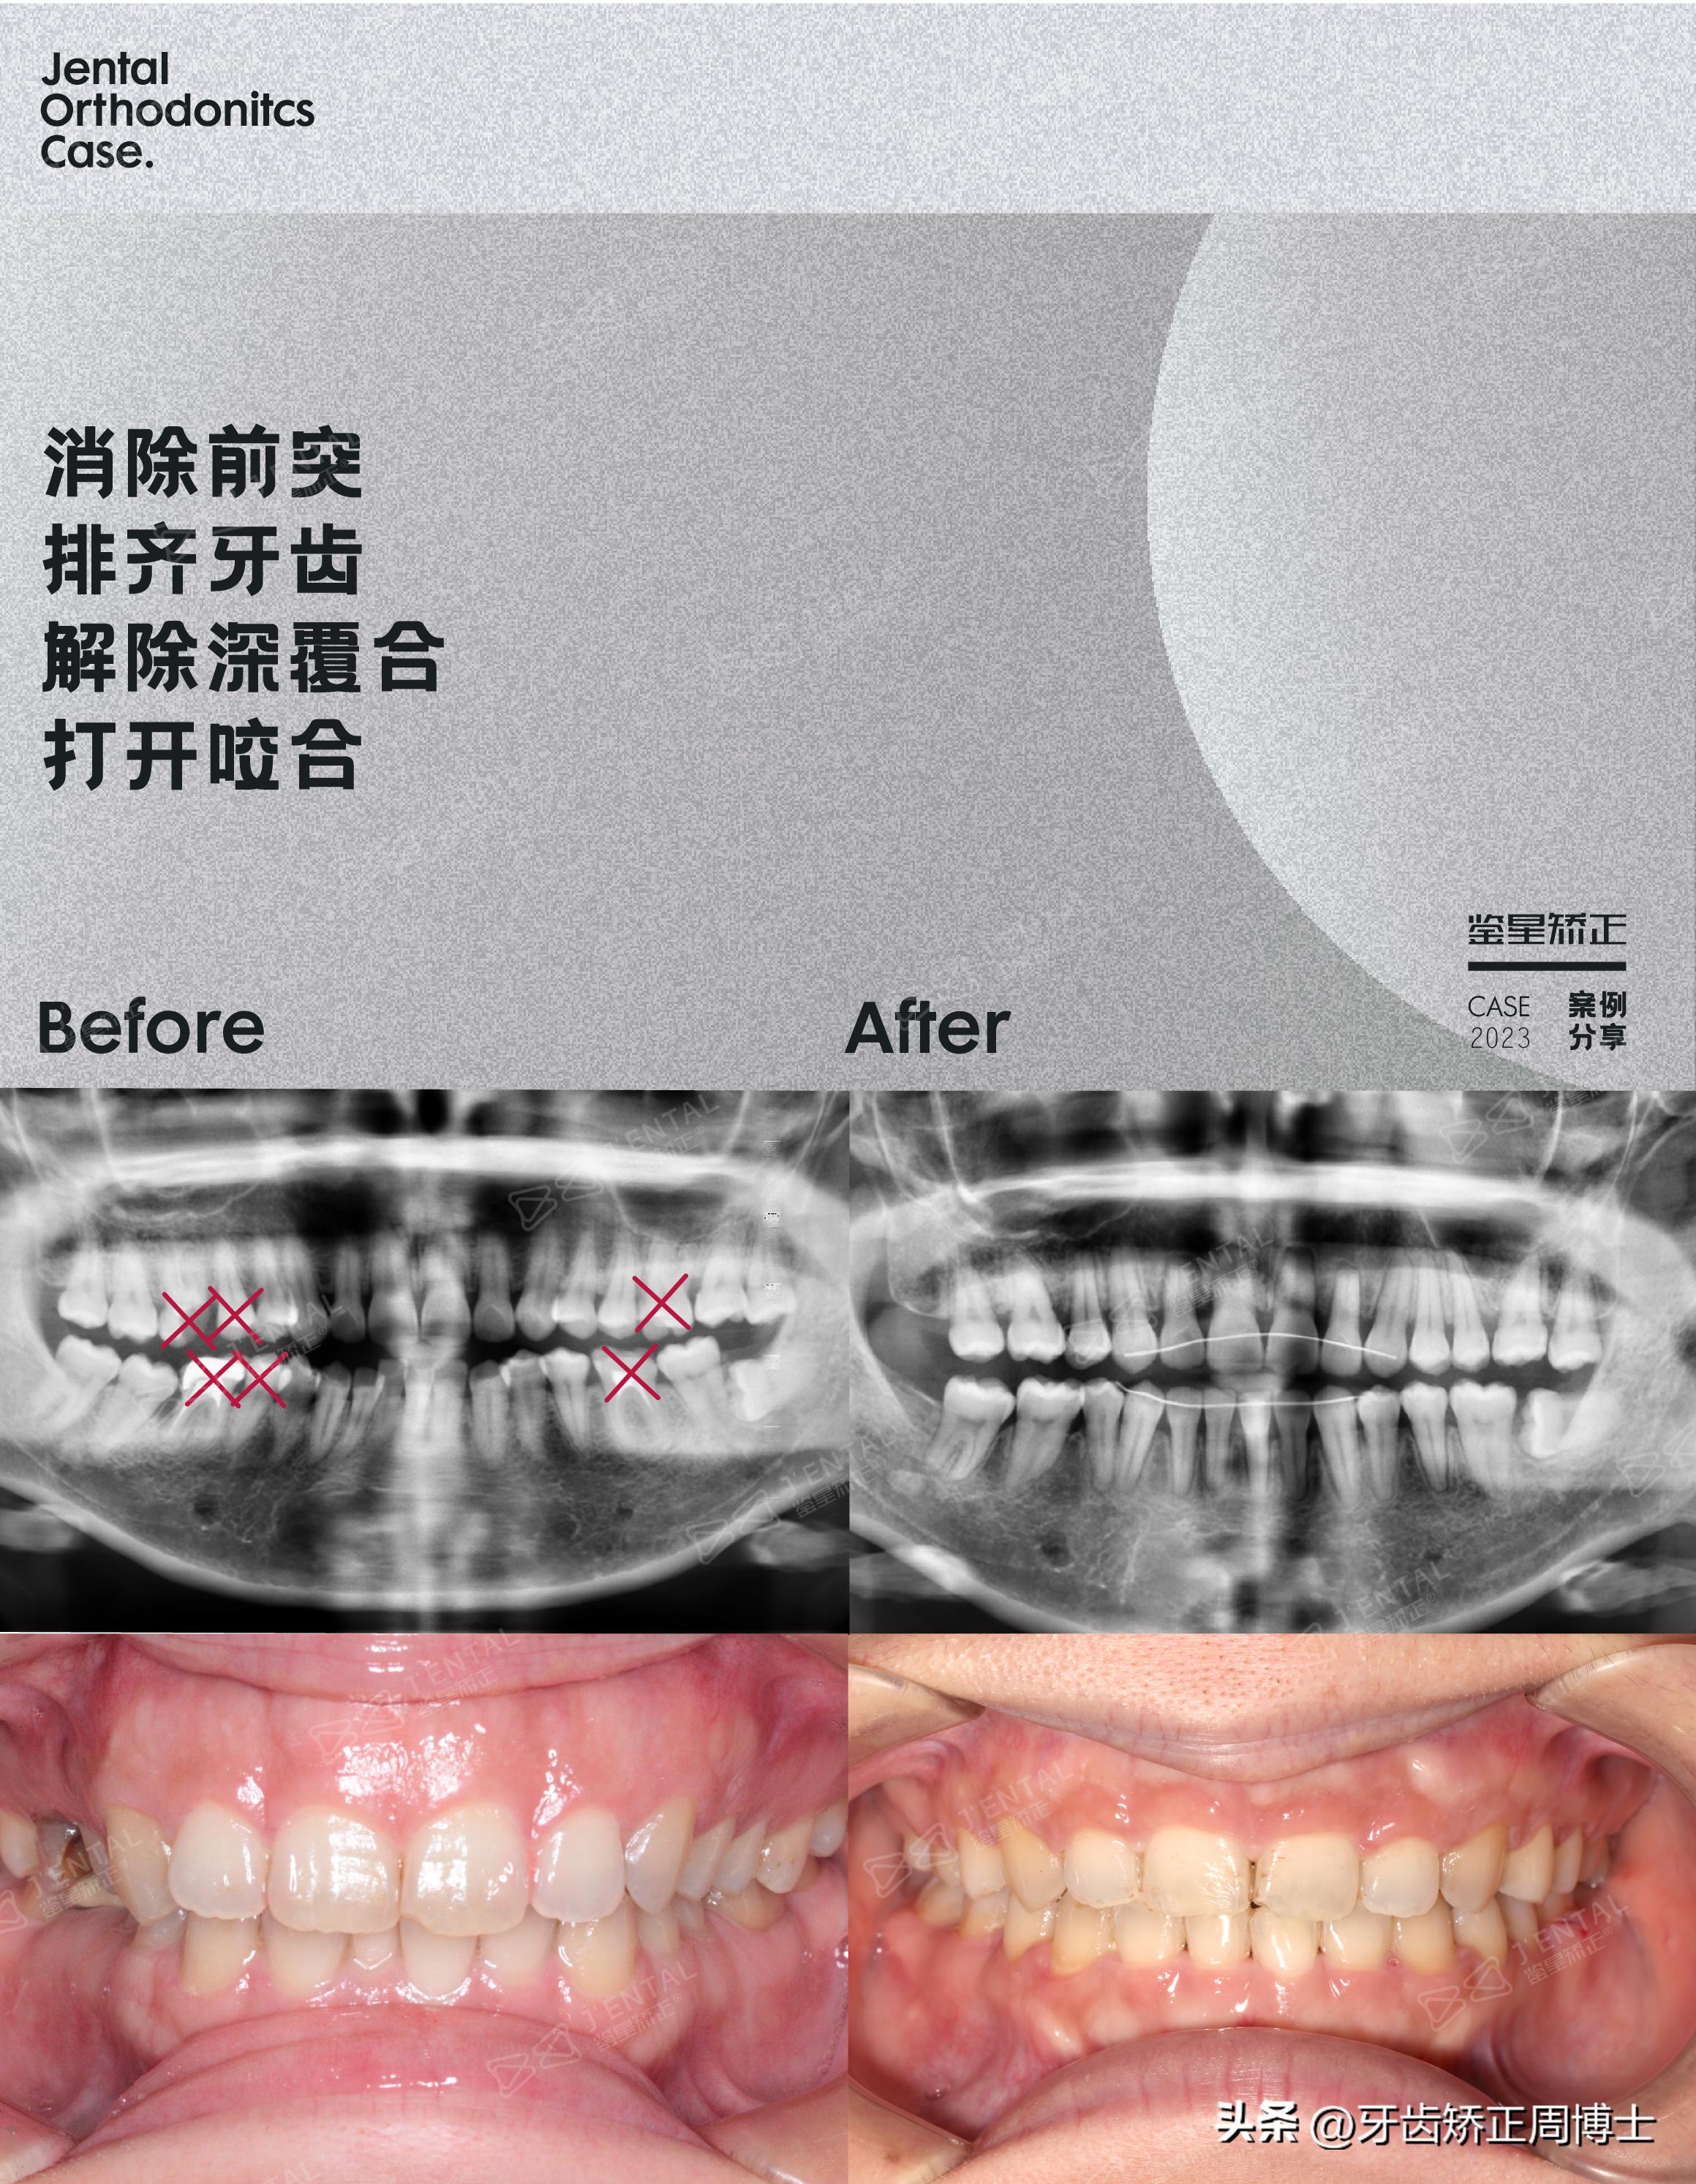

案例概况:超高角骨性前突下巴后缩,MIA全牙列垂直向控制!

方案设计:拔坏牙+智齿替代+8颗支抗钉,MIA全牙列压低!

检查发现,她的上颌前突下巴后缩都属于中等,严重大笑露牙龈,下颌平面角过高,面型为超高角。

26龋坏,16.36.46都是残冠,基于优先拔坏牙原则,设计上下对称,左右不对称的拔牙方案。拔16.26.36.46,术中评估追加拔15.45,再进行智齿替代,2区3区则没有用到智齿提到,干脆做成小牙列。

再通过8颗支抗钉,MIA全牙列压低,解决嘴突,从没下巴做到有下巴,而上牙列压低与下牙列压低的同时进行,这样既可以旋出下巴,又可以保留上前牙的唇展度,从面相照看,虽然人中长,但最终前牙展露度很高。

总用时3年,摇身一变洋气太多!!期间腭杆掉过,因为来一趟比较麻烦,只能等复诊的时候一起处理,虽然也有焦虑难适应的时候,不过过程中会经常拍对比图激励自己,看到变化就一切值得。